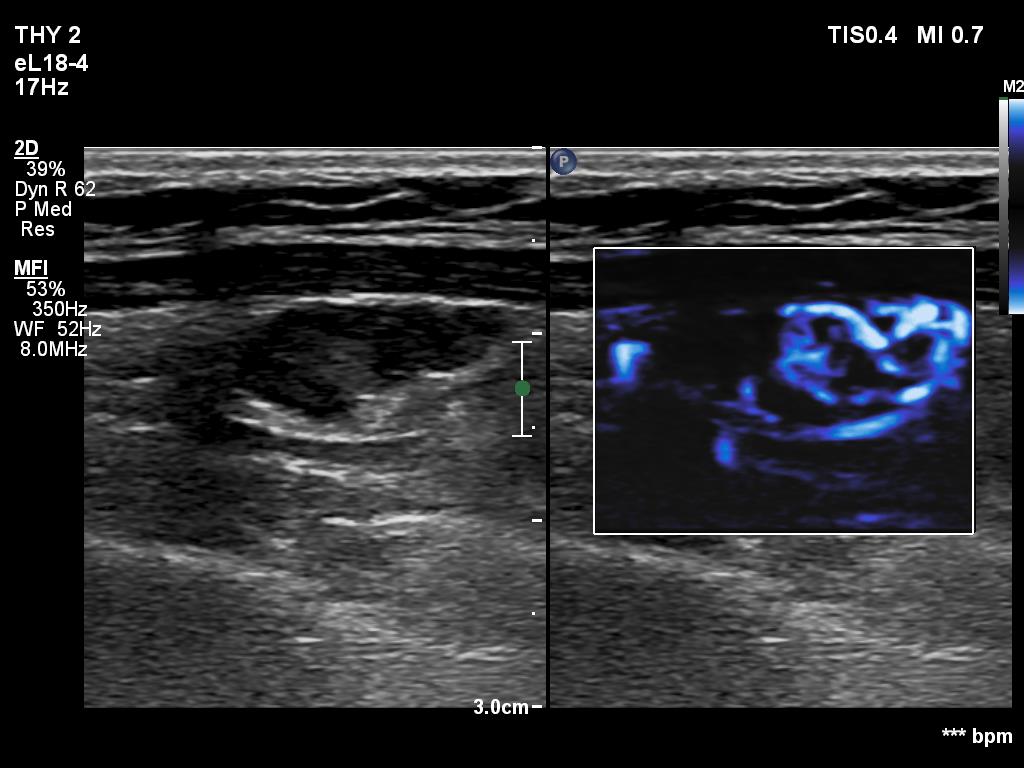

Right lobe, longitudinal scan

Left lobe, longitudinal scan, microflow imaging. The lesion has numerous vessels.